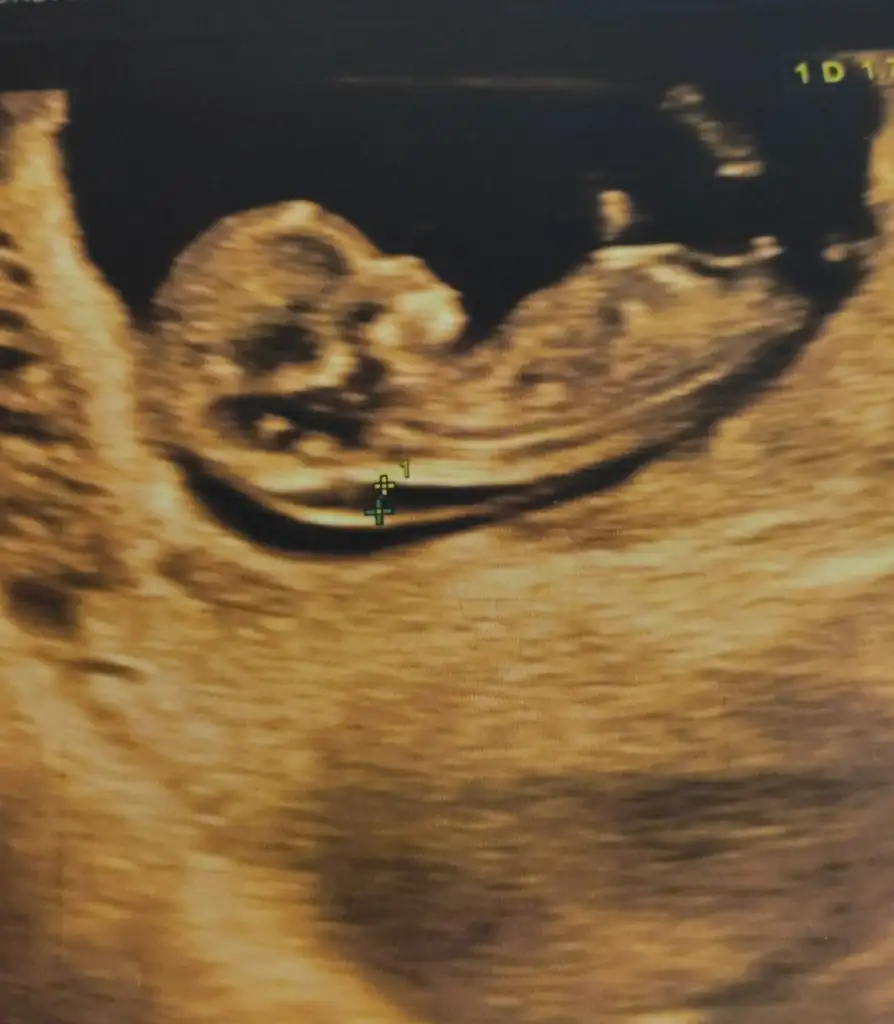

Bayanlar merhaba, nasipse ikinci bebeğimi bekliyorum, annelik her aşamada bambaşka birşey :) ultrason fotoğrafımızı paylaşsam cinsiyet tahmininde bulunur musunuz bizim için de ? 🙏

Başka usgde paylaşın tam net değil nubu 11 12 13 haftalar olmalı sanki kız gibi diyorum şimdilik istediğim haftalarıda paylaşın 😊

Son usg fotosu ve hatta en neti bu 😊 11+5 te gitmiştik en son kontrole, iki hafta sonra yeniden gideceğiz, o zamanki o de paylaşırım teşekkür ederim 🙏